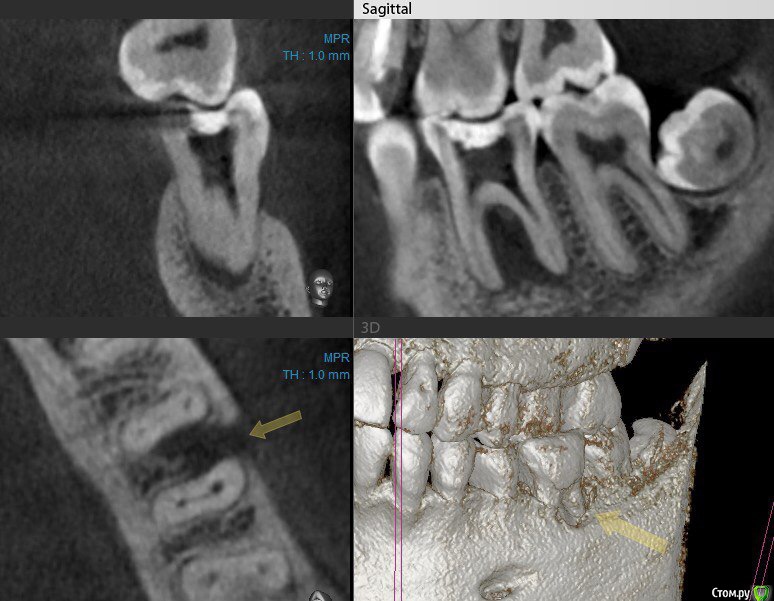

cor Опубликовано 2 апреля, 2016 Поделиться Опубликовано 2 апреля, 2016 Доброго времени суток, коллеги! Каков Ваш прогноз? Удалять пац. совсем не хочет(знакомая). Есть хоть какая то вероятность, что ретрит поможет? <script> </script> Ссылка на комментарий

cor Опубликовано 2 апреля, 2016 Поделиться Опубликовано 2 апреля, 2016 (изменено) гадская вирусятина на компе мешает. Нет конечно желающих. Но если ретрит будет, то делать его буду я. Но слабо верю в положительный исход(( Изменено 2 апреля, 2016 пользователем cor Ссылка на комментарий

Гарриевич Опубликовано 3 апреля, 2016 Поделиться Опубликовано 3 апреля, 2016 Доброго времени суток, коллеги! Каков Ваш прогноз? Удалять пац. совсем не хочет(знакомая). Есть хоть какая то вероятность, что ретрит поможет? шансов не меньше чем тут Ссылка на комментарий

St. Опубликовано 3 апреля, 2016 Поделиться Опубликовано 3 апреля, 2016 Доброго времени суток, коллеги! Каков Ваш прогноз? Удалять пац. совсем не хочет(знакомая). Есть хоть какая то вероятность, что ретрит поможет? Вполне есть смысл попробовать. Вероятность есть, только "заживать" будет долго. Ссылка на комментарий

cor Опубликовано 5 апреля, 2016 Поделиться Опубликовано 5 апреля, 2016 Почему?Наверное потому что такие объемные очаги ещё не перилечивал. Но деваться некуда, будем пробовать. Ссылка на комментарий

Л Ю С Я Опубликовано 5 апреля, 2016 Поделиться Опубликовано 5 апреля, 2016 Наверное потому что такие объемные очаги ещё не перилечивал. Но деваться некуда, будем пробовать.Уже не раз писали, что размер не имеет значения)))). Не надо перелечивать очаг. Ваша задача пройти, правильно сформировать, очистить и запаковать каналы, а также правильно восстановить коронковую часть. И будет вам хилинг))) 2 Ссылка на комментарий